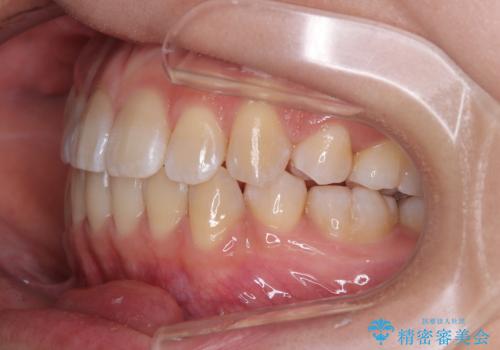

非接触の前歯と下顎のデコボコ ワイヤー装置による矯正治療

- 上下顎前歯部の非接触(開咬)と下顎のデコボコを主訴に来院された患者様です。

右側上下と左上の小臼歯が一本ずつ少なく、さらに骨格的な左右差もあり上下の真ん中の位置がずれています。

下顎のデコボコの解消と、真ん中の位置を改善するために左下の小臼歯を抜歯することとしました。

また、開咬を改善するため臼歯部にアンカースクリューを用いて圧下する力をかけていきました。

舌を突出する癖があり、それにより開咬が悪化したり、後戻りの原因になるため、舌のトレーニング(MFT)も行いました。